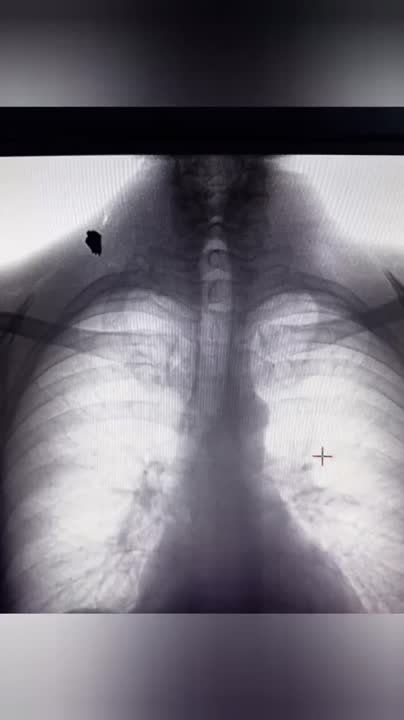

Врачи ФМБА России продолжают оказывать медицинскую помощь на новых территориях. В Херсонской области специалисты спасли мужчину, который получил ранение в спину.С помощью мобильного флюрографа ФМБА России медики обнаружили у пациента осколок. Они...